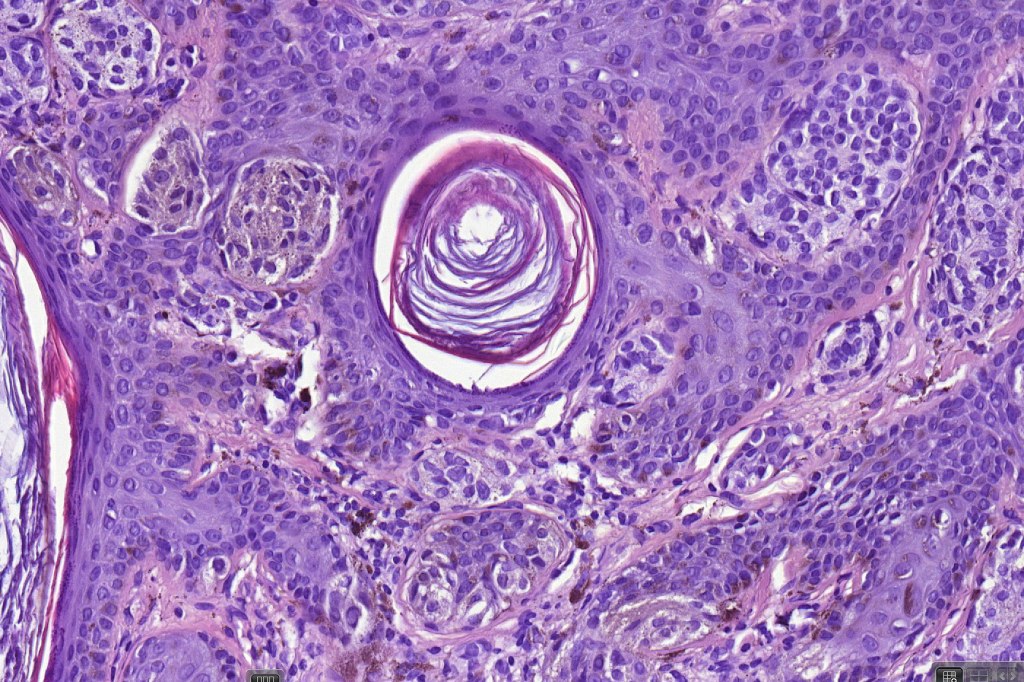

•Hyperkeratosis, & acanthosis sometimes present, otherwise epidermis of normal thickness

•Usually compound nevus with intense infiltration by lymphocytes, histiocytes and occasional plasma cells, in particularly florrid examples immunohistchemistry may be necessary to identify the nevus cells

•Nevus cells often show degenerative atypia (nuclear pleomorphism, hyperchomatism & sometimes fine granular pigmentation (gray or gray/green)

•Melanophages present particularly in older lesions